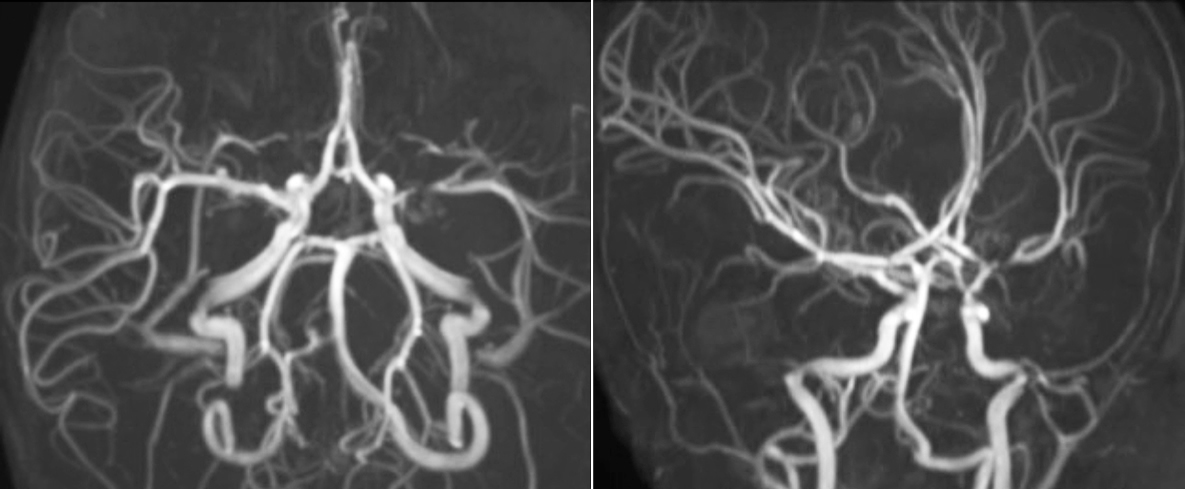

Pseudo-continuous arterial spin labeling (pCASL) was developed for brain perfusion imaging without contrast agent. “This is very desirable in pediatric patients where the general trend is to limit the administration of contrast,” says Dr. Miller. Growing confidence in specific applications “We built up confidence in pCASL by comparing it to contrast-based perfusion imaging. Once we had confidence that it was representing what the contrast perfusions were representing, we increased our diagnostic confidence by serial imaging in either the acute stage or the long term stages in a number of patients with arterial abnormalities.

“In combination with diffusion weighted imaging, it can help give a more extended assessment of the degree of perfusion abnormality in a patient who is suffering acute ischemia. We have a number of patients who have chronic arterial insufficiency due to prior arterial abnormalities or acquired arterial abnormalities such as sickle cell disease or neurofibromatosis. Sometimes the child’s first manifestation of disease progression is a reduction in brain perfusion before stroke symptoms manifest clinically or in diffusion weighted imaging. We use pCASL to help delineate the perfusion abnormality.”

To other new users I would recommend to also start to interpret the pCASL images in comparison with other standard imaging – T2 and FLAIR and DWI – until the user gains confidence in interpreting these images by themselves.” “A powerful use of pCASL is in patients with chronic cerebrovascular stenosis, where clinicians desire information on how compensatory mechanisms of the brain are performing to enable perfusion to the brain. Often clinicians take into account how the compensatory mechanisms appear to help to provide adequate perfusion to the patient’s brain, and they may intervene surgically or make some other management decision.” “Another special application is the assessment of cerebrovascular reactivity with a Diamox perfusion exam, where we subtract two sets of pCASL images.”